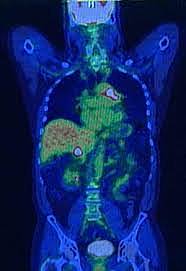

• First PET Invented

First PET Invented

In 1973, 3 scientists, Edward Hoffman, Michael M. Ter-Pogossian, and Michael E. Phelps, invented the PET scan which is an imaging test to see how a persons organs and body functions and can help detect diseases before they show up.